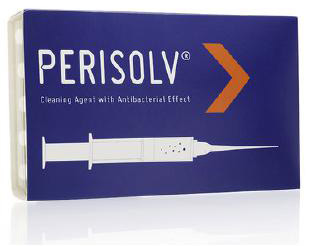

神経の治療を行ったのにも関わらず歯根の先端に膿が溜まってしまう場合は、通常の治療では届かない場所に細菌が感染している可能性が考えられます。歯根の先端3㎜の部分には、通常の器具が届かない神経の枝分かれが存在することがあり、外科治療によって取り除くしか感染源を除去する方法がありません。

歯根端切除術では、フラップ手術と同様に歯ぐきを剥離して歯根の先端を露出させ、歯根の先端3㎜を除去した後、特殊なセメントを断面に詰めて縫合します。